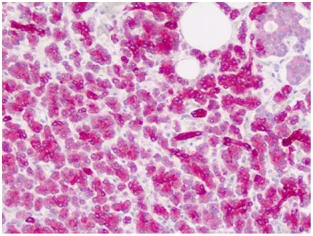

Immunohistochemistry (Formalin/PFA-fixed paraffin-embedded sections) - Anti-ZIC4 antibody - C-terminal (AB178512)

Immunohistochemical analysis of ZIC4 expression in paraffin embedded, formalin fixed Human pancreas tissue using ab178512 at 10 μg/ml dilution.